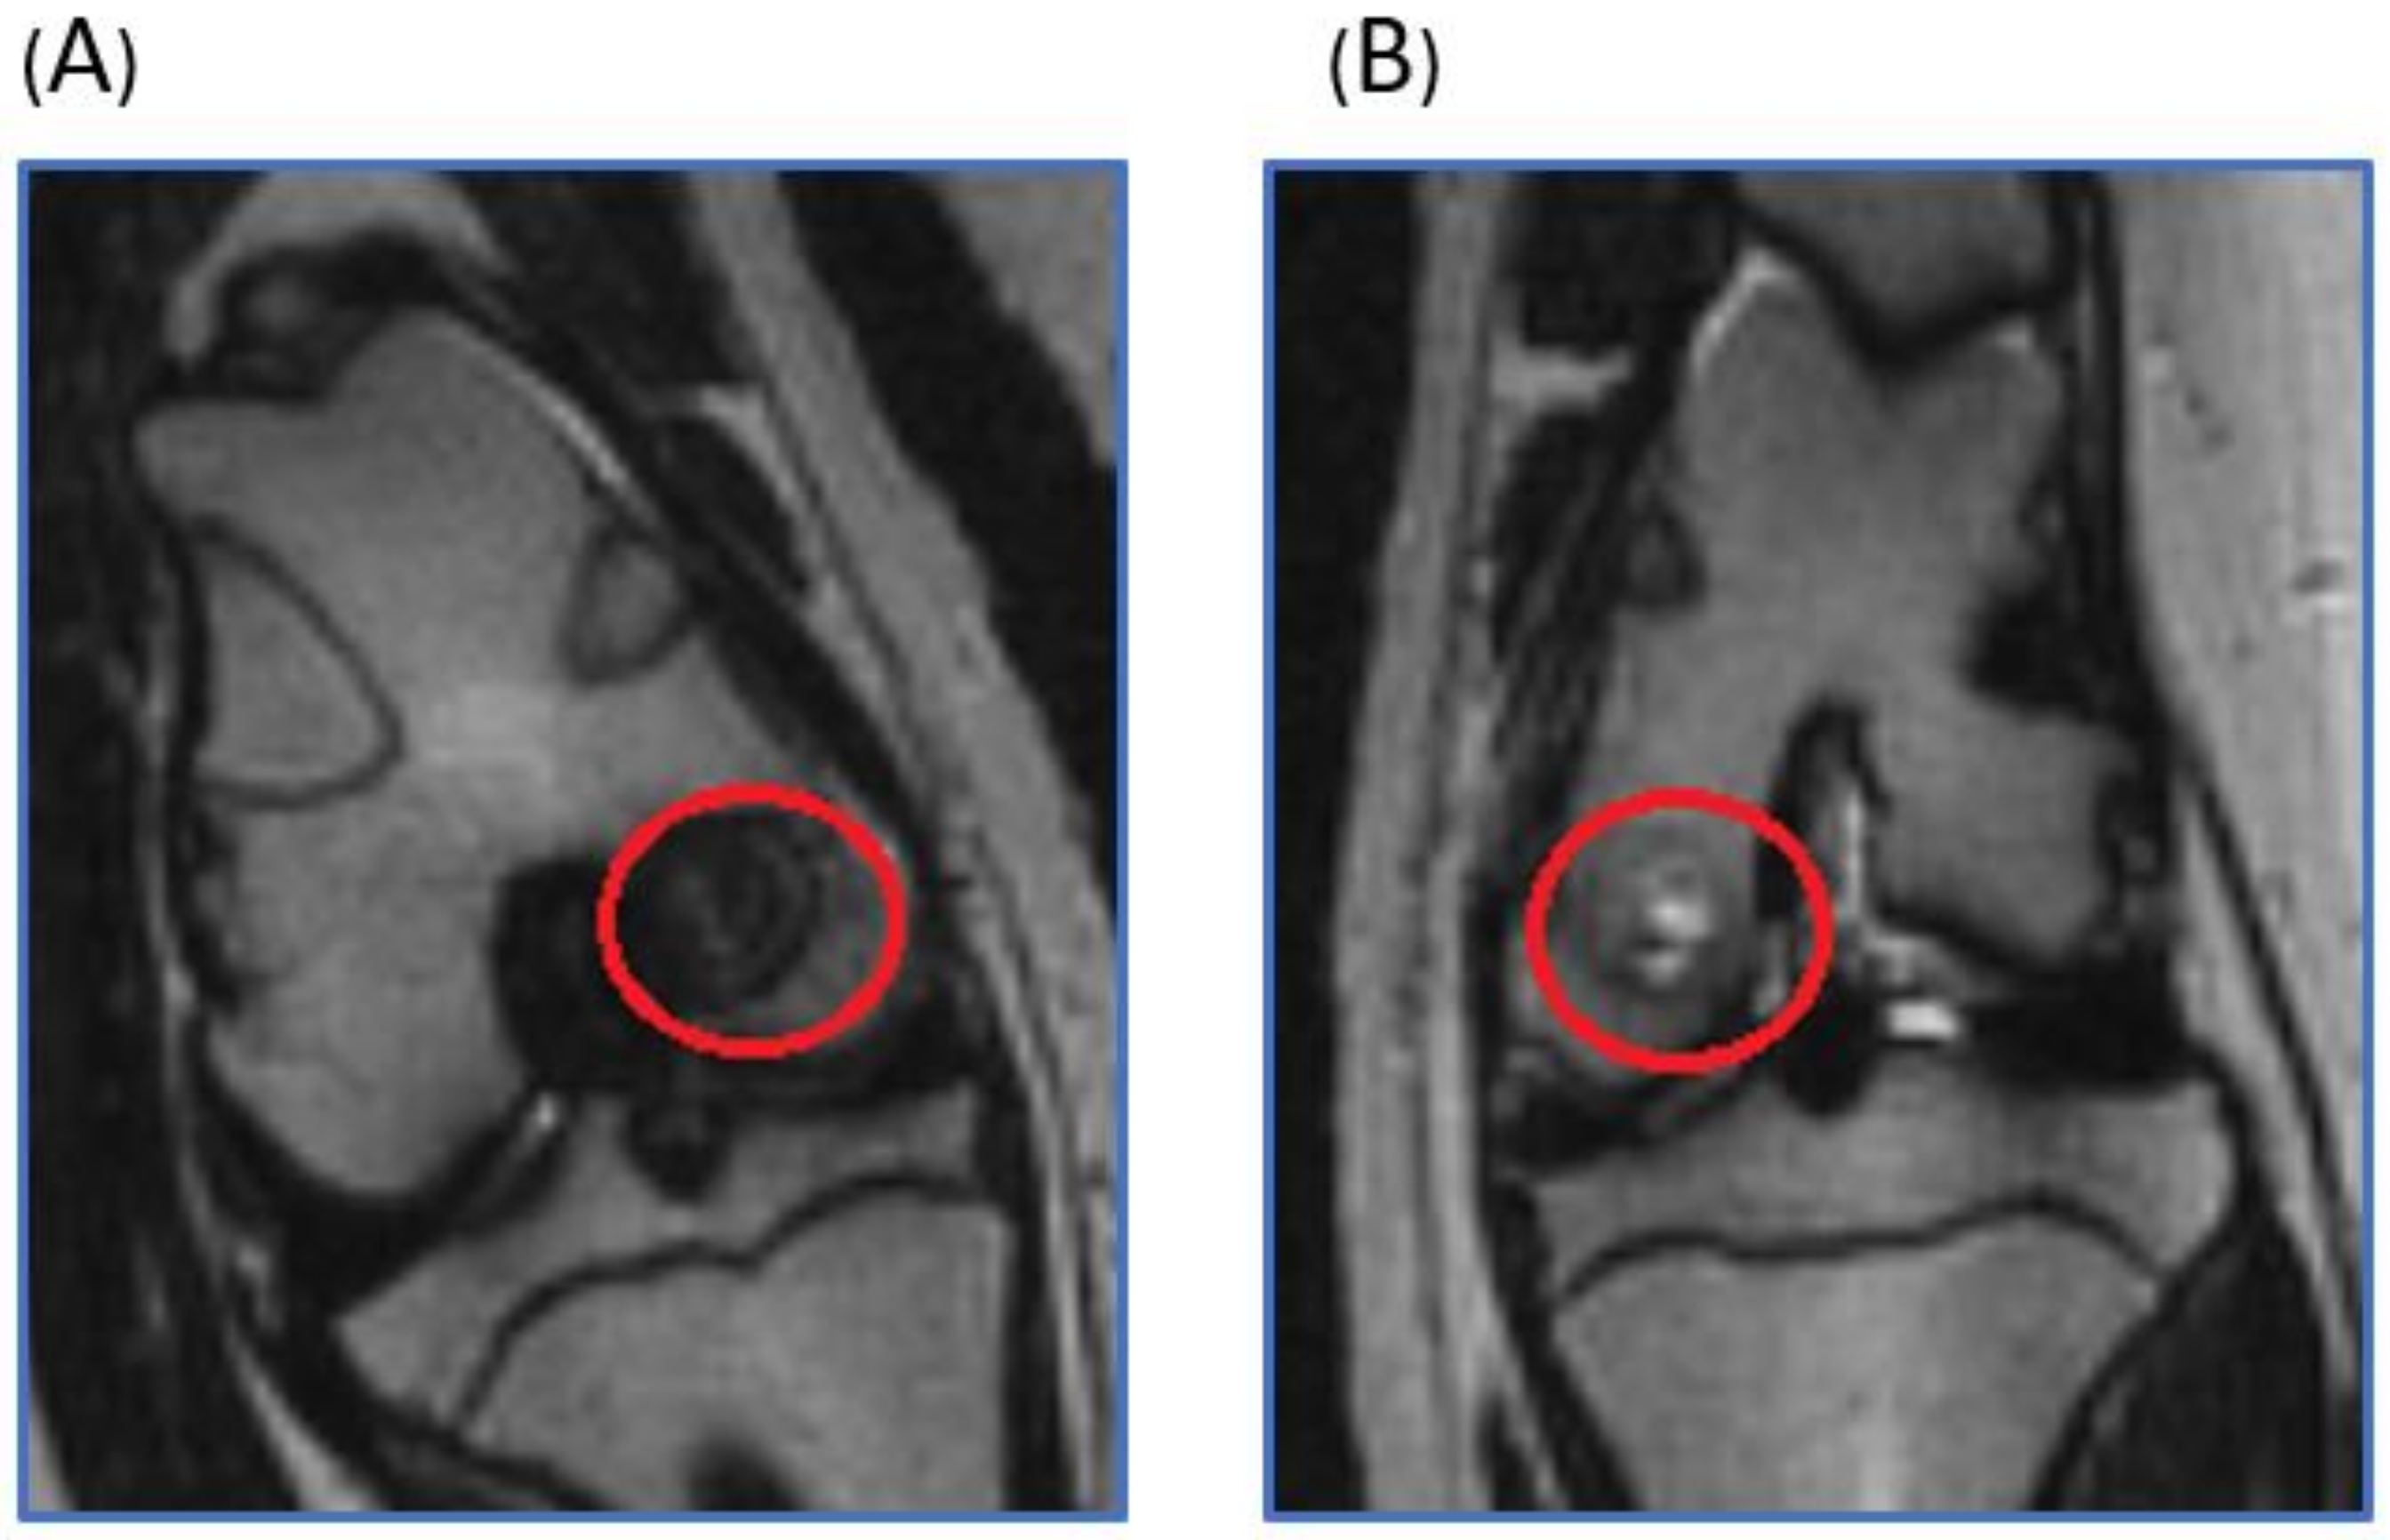

2.1. Live Magnetic Resoance Imaging (MRI) Monitoring of Articular Cartilage Repair in Minipigs